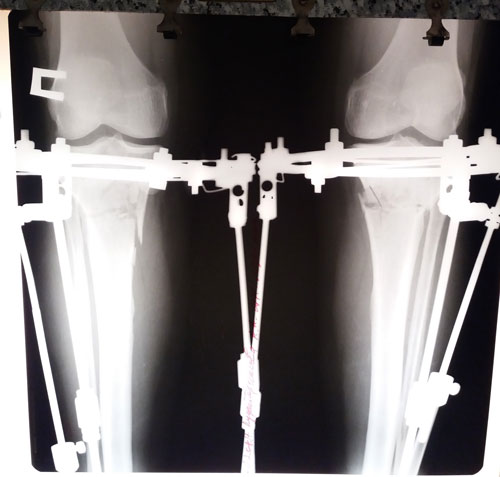

Ножки на сращении.

Вложения

IMG-20170905-WA0012.jpg